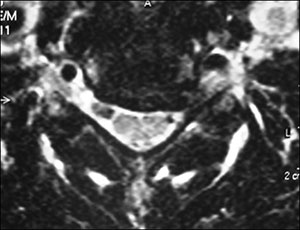

Dentre os exames de imagem, a ressonância magnética (RM) é o exame de escolha para avaliação da compressão radicular (Fig. 2). Entre as inúmeras vantagens do método é possível citar: exames contrastantes em T1 e T2, sem uso de radiação ionizante, ótima definição das estruturas neurais e das partes moles (Fig. 5). Quando a RM não for disponível, a tomografia computadorizada (TC) ou a mielotomografia (realizada com contraste) podem ser úteis (Fig. 3).

Fig. 2. Imagem axial em T2 de RNM de doente com hérnia cervical comprimindo a raíz de C6.